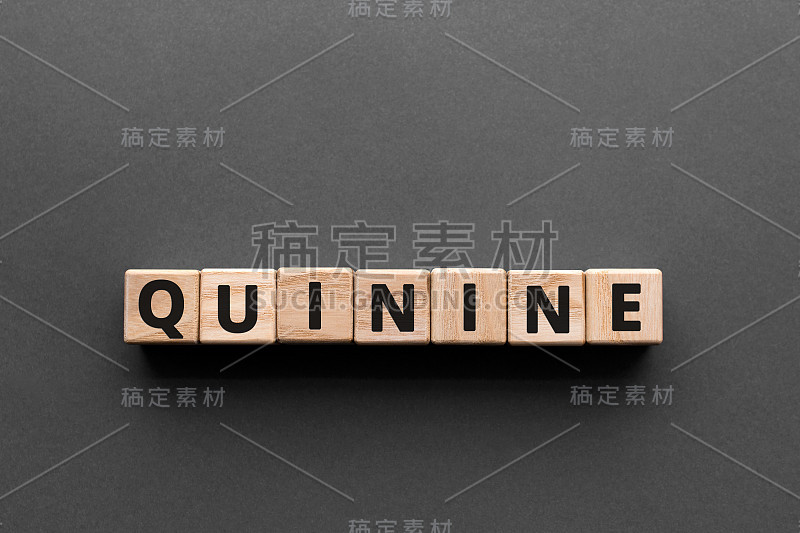

奎宁-木块上的字母详情